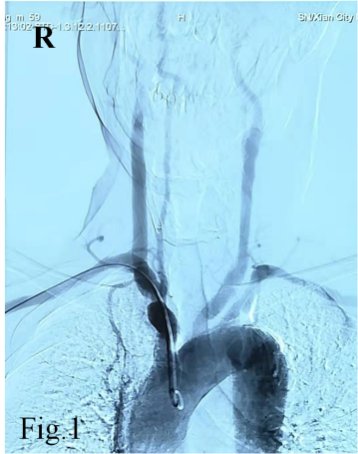

经过导丝引导下,谨慎地将造影导管置于主动脉弓,造影显示Ⅱ型主动脉弓,介入医生顿感压力倍增。常规路径下(股动脉置管),Ⅱ型主动脉弓要比Ⅰ型主动脉弓操作难度复杂的多,颈部血管从主动脉弓发出角度、走形、迂曲度及造影导管在主动脉弓如何塑形、塑形成功率等等都会制约操作时间、顺畅性,稍有不慎可能导致主动脉弓斑块脱落、主动脉动脉夹层等情况发生。增加了在经桡动脉在Ⅱ型主动脉弓上超选造影的难度。经介入医生耐心、细致操作下,反复尝试降主动脉造影导管成型,逐步“逆行”完成全脑血管造影及下肢动脉造影。